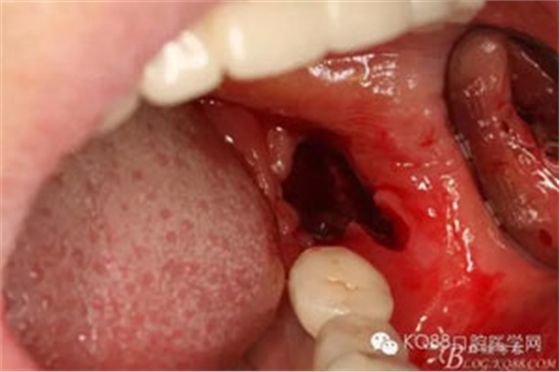

圖9. 清理拔除38的拔牙創(chuàng)口